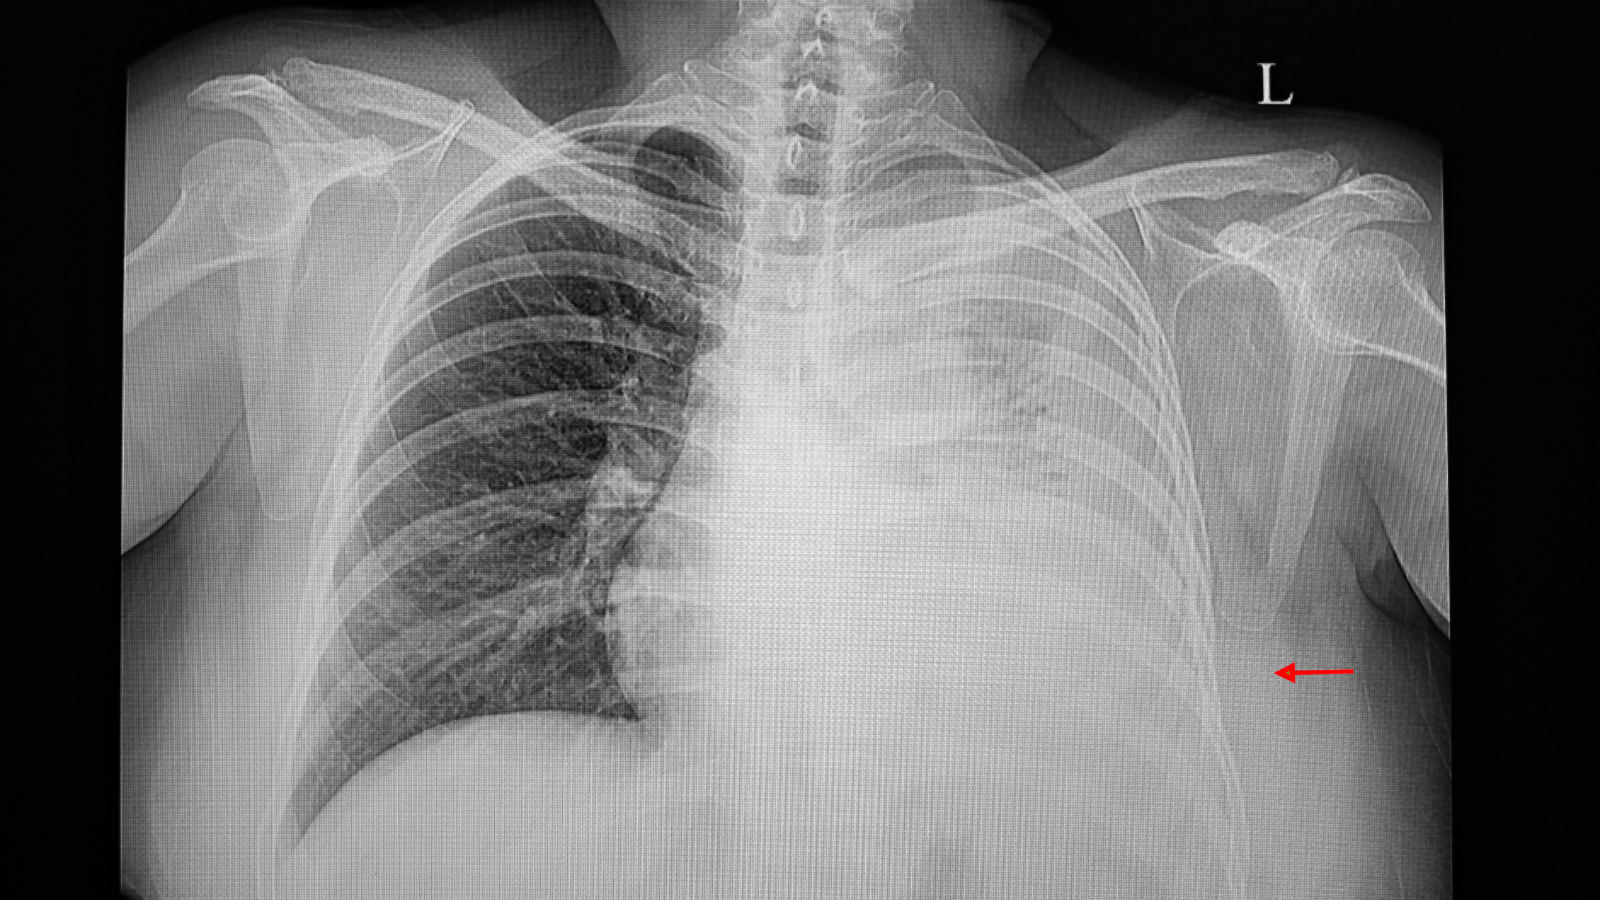

Chụp X - quang phổi

Đây là bước thăm khám đầu tiên khi nghi ngờ có dịch trong khoang màng phổi. Hình ảnh X - quang giúp phát hiện vùng mờ ở đáy phổi, dấu hiệu đặc trưng của tràn dịch. Tuy nhiên, phương pháp này chỉ phát hiện được khi lượng dịch đã tương đối nhiều và không thể xác định bản chất của dịch là lành hay ác tính.